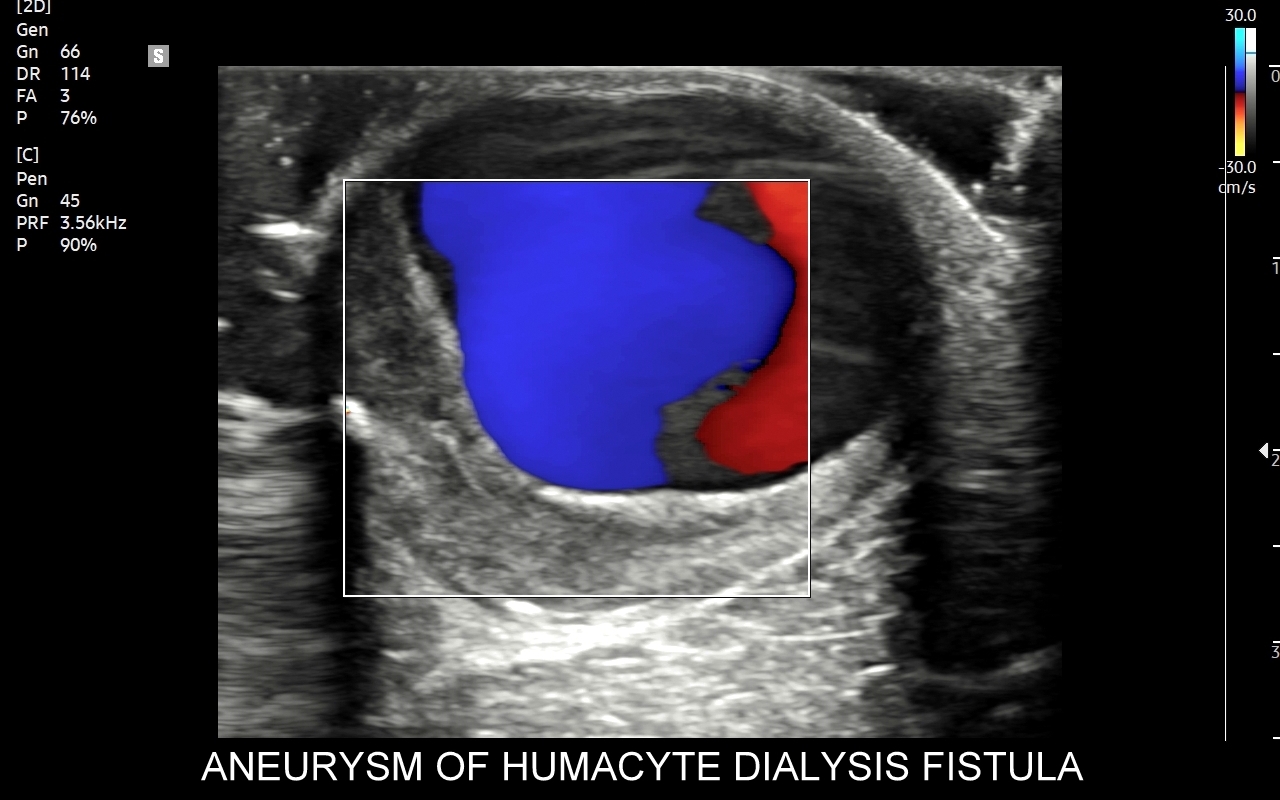

USG przetok dializacyjnych

Przetoka dializacyjna to chirurgicznie wytworzone połączenie tętniczo-żylne, które wykorzystywane jest do przewlekłego leczenia nerkozastępczego w formie hemodializy u pacjentów z niewydolnością nerek. Badanie USG Doppler jest podstawową metodą diagnostyczną oceniającą dojrzałość przetoki i jej gotowość do dializy, prawidłowość zespoleń naczyniowych, drożność przetoki oraz objętość przepływu minutowego. W Pracowni dr Tomasza Szczepańskiego zbadać można klasyczne przetoki tętniczo-żylne, jak również zaawansowane przetoki Humacyte ®.